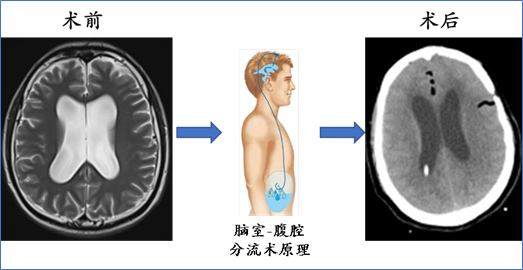

4.脑室-腹腔分流术:

目的:解除脑积水、降低颅内压力、缓解症状,为后续治疗创造条件;

适应症:脑转移、脑膜转移引发脑积水的患者

脑室-腹腔分流手术病例